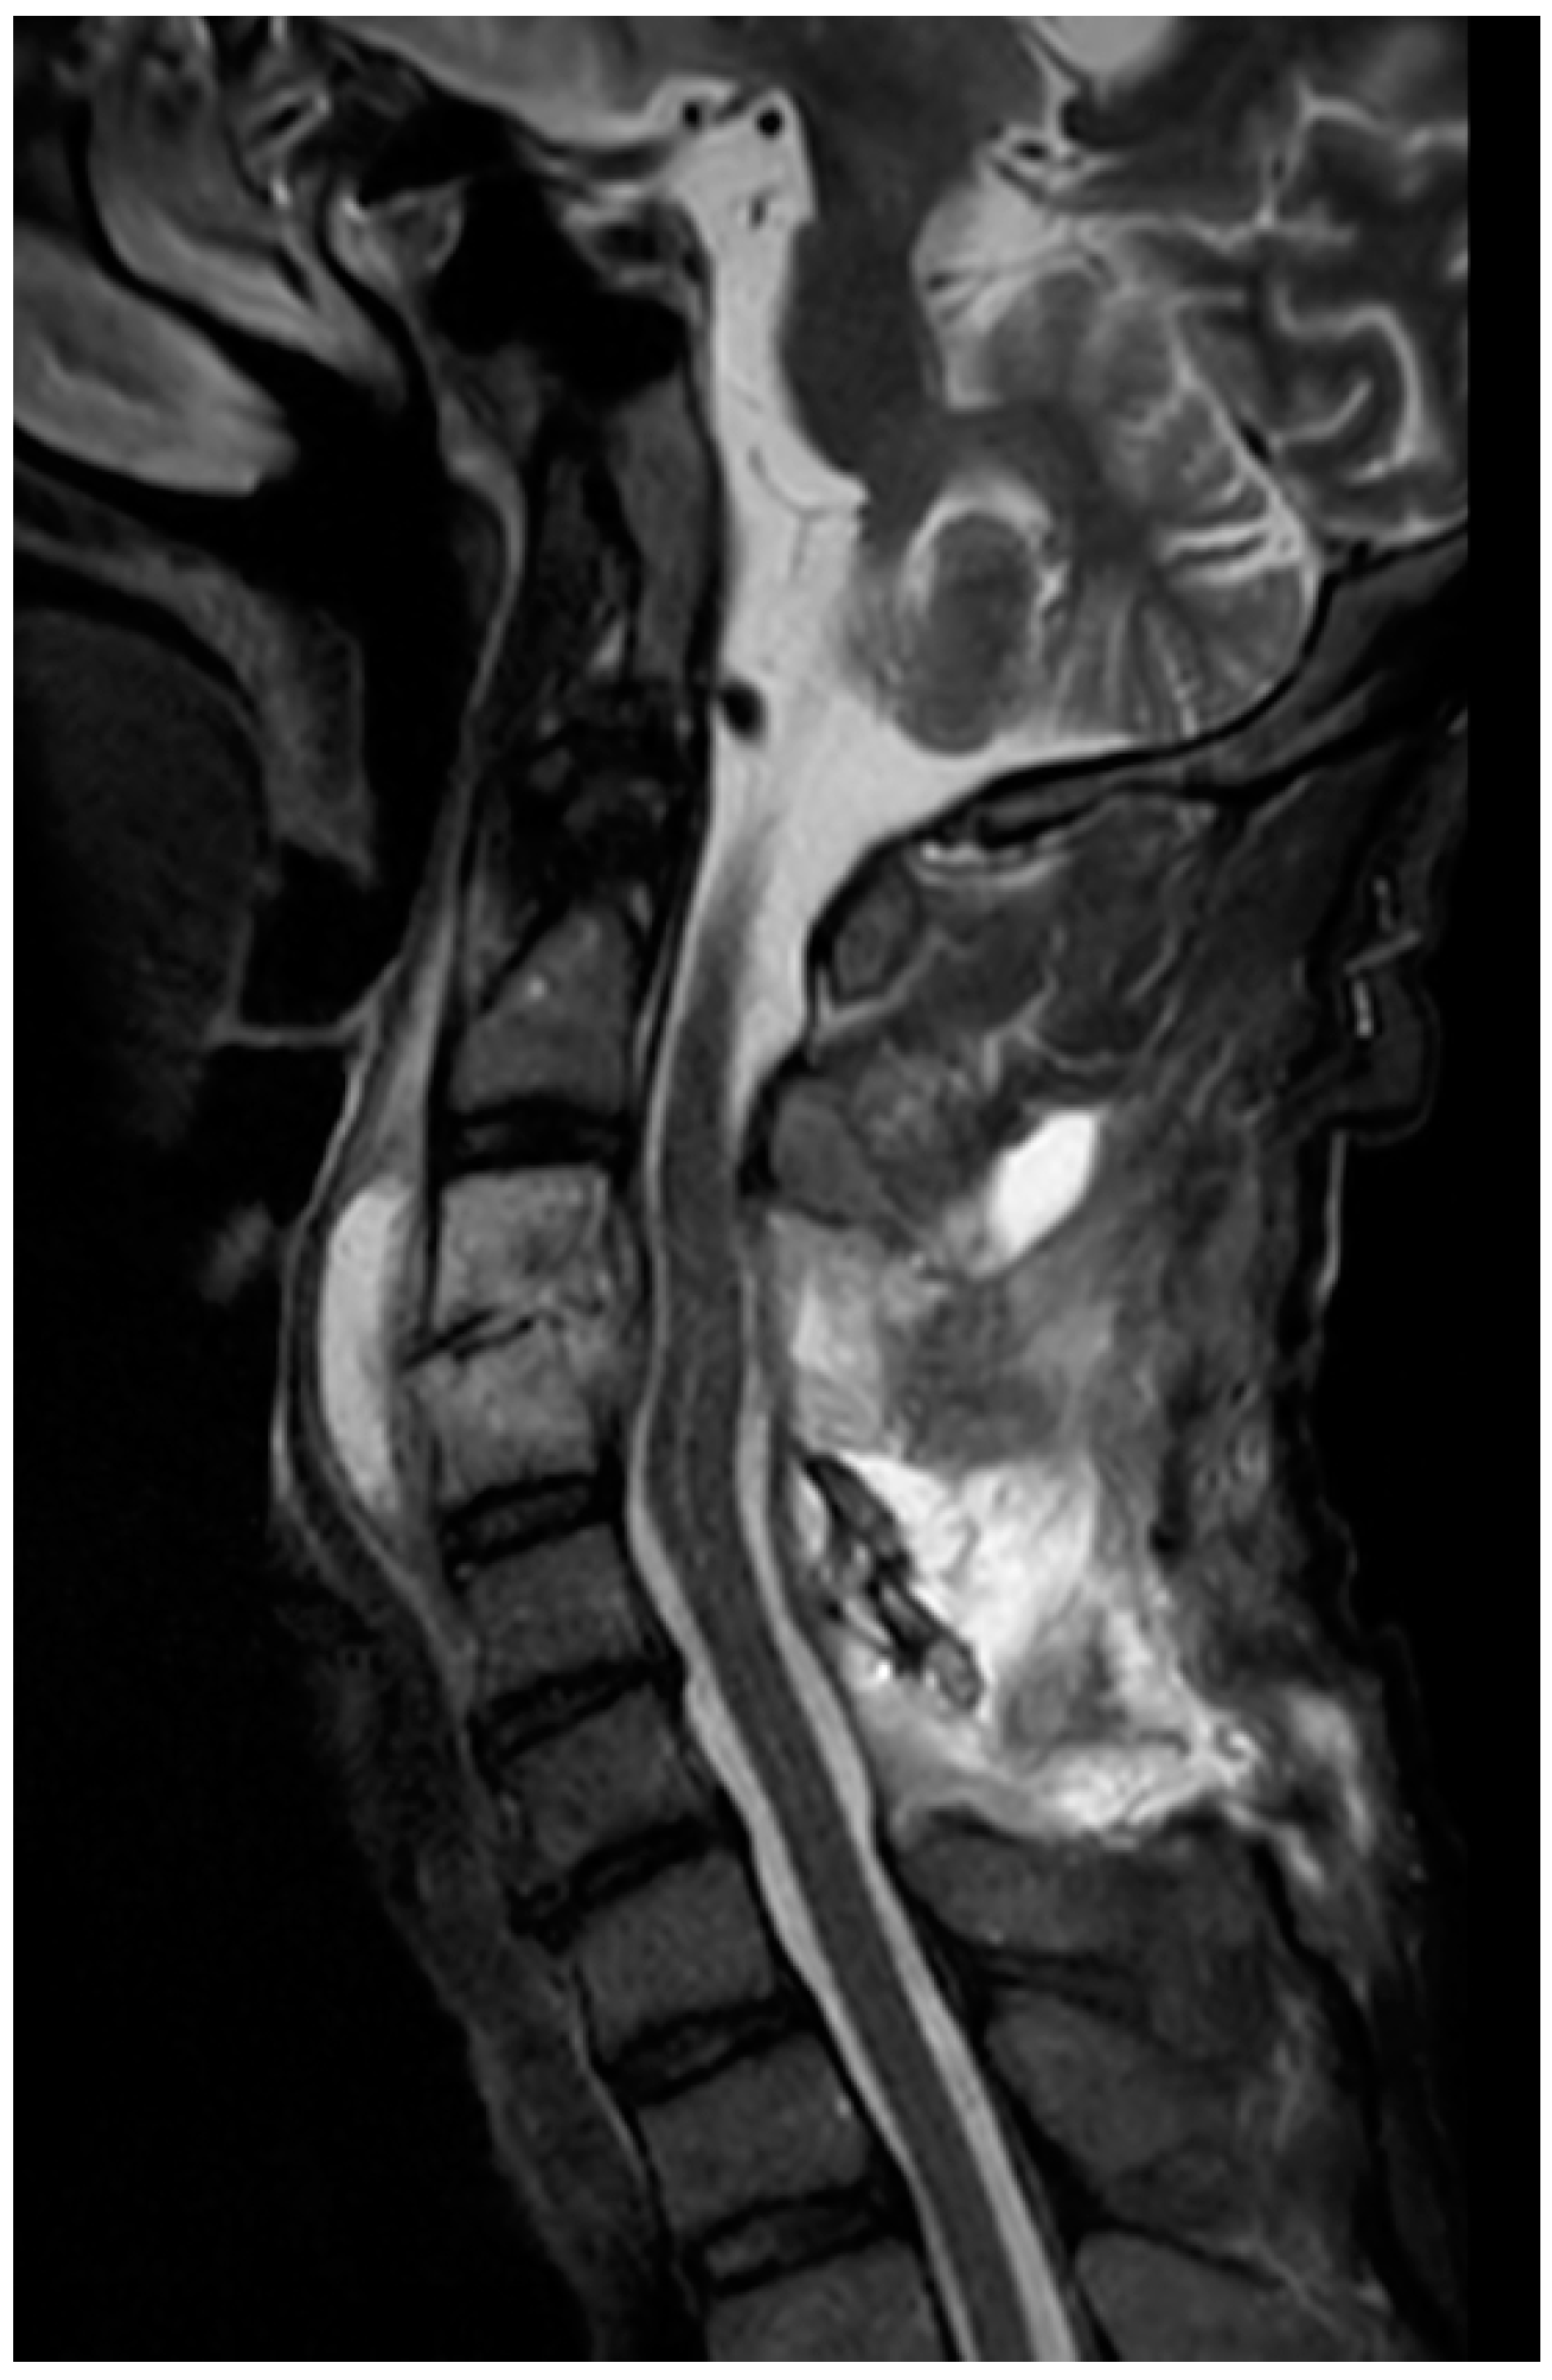

Cervical Epidural Abscess Secondary to a Post-Traumatic Hematoma, Successfully Treated with Adjunctive Hyperbaric Oxygen Therapy: A Case Report

2. Case Presentation